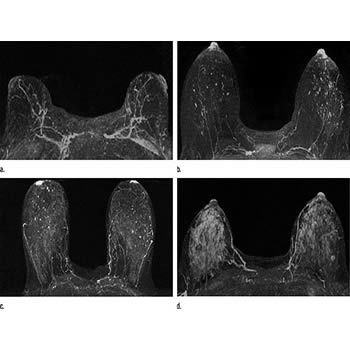

If these tests don't answer the quest. But not every woman who has been diagnosed with breast cancer needs a breast mri. Determining the extent of cancer after a new breast cancer diagnosis. It can also help detect breast cancer in women with breast implants and in younger women who tend to have dense breast tissue. An mri can be used to look for a disease, such as breast cancer. But there are also other reasons to have a breast mri. Inflammatory breast cancer affects breast tissue and can appear unusually dimpled or thick. Breast mri images are combined, using a computer, to create detailed pictures. A waiver of informed consent Mri scan is also used in breast screening for young women who are at higher risk of developing cancer. Dcis on mri may create an area of irregular enhancement of the mri dye into the breast. They're often easy to move around (mobile) and may be tender. A breast mri is a highly effective test.

Lobular breast cancer can be more difficult to see on imaging and scans. Recent research has found that mri can locate some small breast lesions sometimes missed by mammography. Your doctor may recommend a breast mri for the following: The dye collection in the breast can also look clumpy or appear in a section of the breast, depending on the involvement of dcis. Some benign conditions such as fibrocystic disease can look like cancer.

The Radiology Assistant Mri Of The Breast from radiologyassistant.nl Your doctor may recommend a breast mri for the following: A breast mri captures multiple images of your breast. This is why we ask questions about menstrual cycle and hormone therapies prior to your study. What does breast cancer look like on a mammogram? Dcis on mri may create an area of irregular enhancement of the mri dye into the breast. The features of a malignant breast condition on mri scan are often to do with the outer irregular borders of a lesion. An mri can be used to look for a disease, such as breast cancer. If you are at risk of getting a certain disease, your caregiver may want to do an mri to look for signs of the disease.

An mri can help find a disease of the lungs or show tumors (growths) in the chest. But not every woman who has been diagnosed with breast cancer needs a breast mri. The features of a malignant breast condition on mri scan are often to do with the outer irregular borders of a lesion. A rash isn't the only visual symptom of inflammatory breast cancer. Any area that does not look like normal tissue is a possible cause for concern. A breast mri scan might also be used to assess the size of the cancer to check which kind of surgery is possible. They work to destroy the tumor or slow down the growth of cancer cells. This appears most commonly as streaking, known as linear enhancement. On the flip side, there are benign (not cancerous) breast changes which can mimic breast cancer as well. This means that the test finds a mass or other change that seems to show cancer but it is not cancer. Breast mri images are combined, using a computer, to create detailed pictures. What does breast cancer look like on a mammogram? The dye collection in the breast can also look clumpy or appear in a section of the breast, depending on the involvement of dcis.